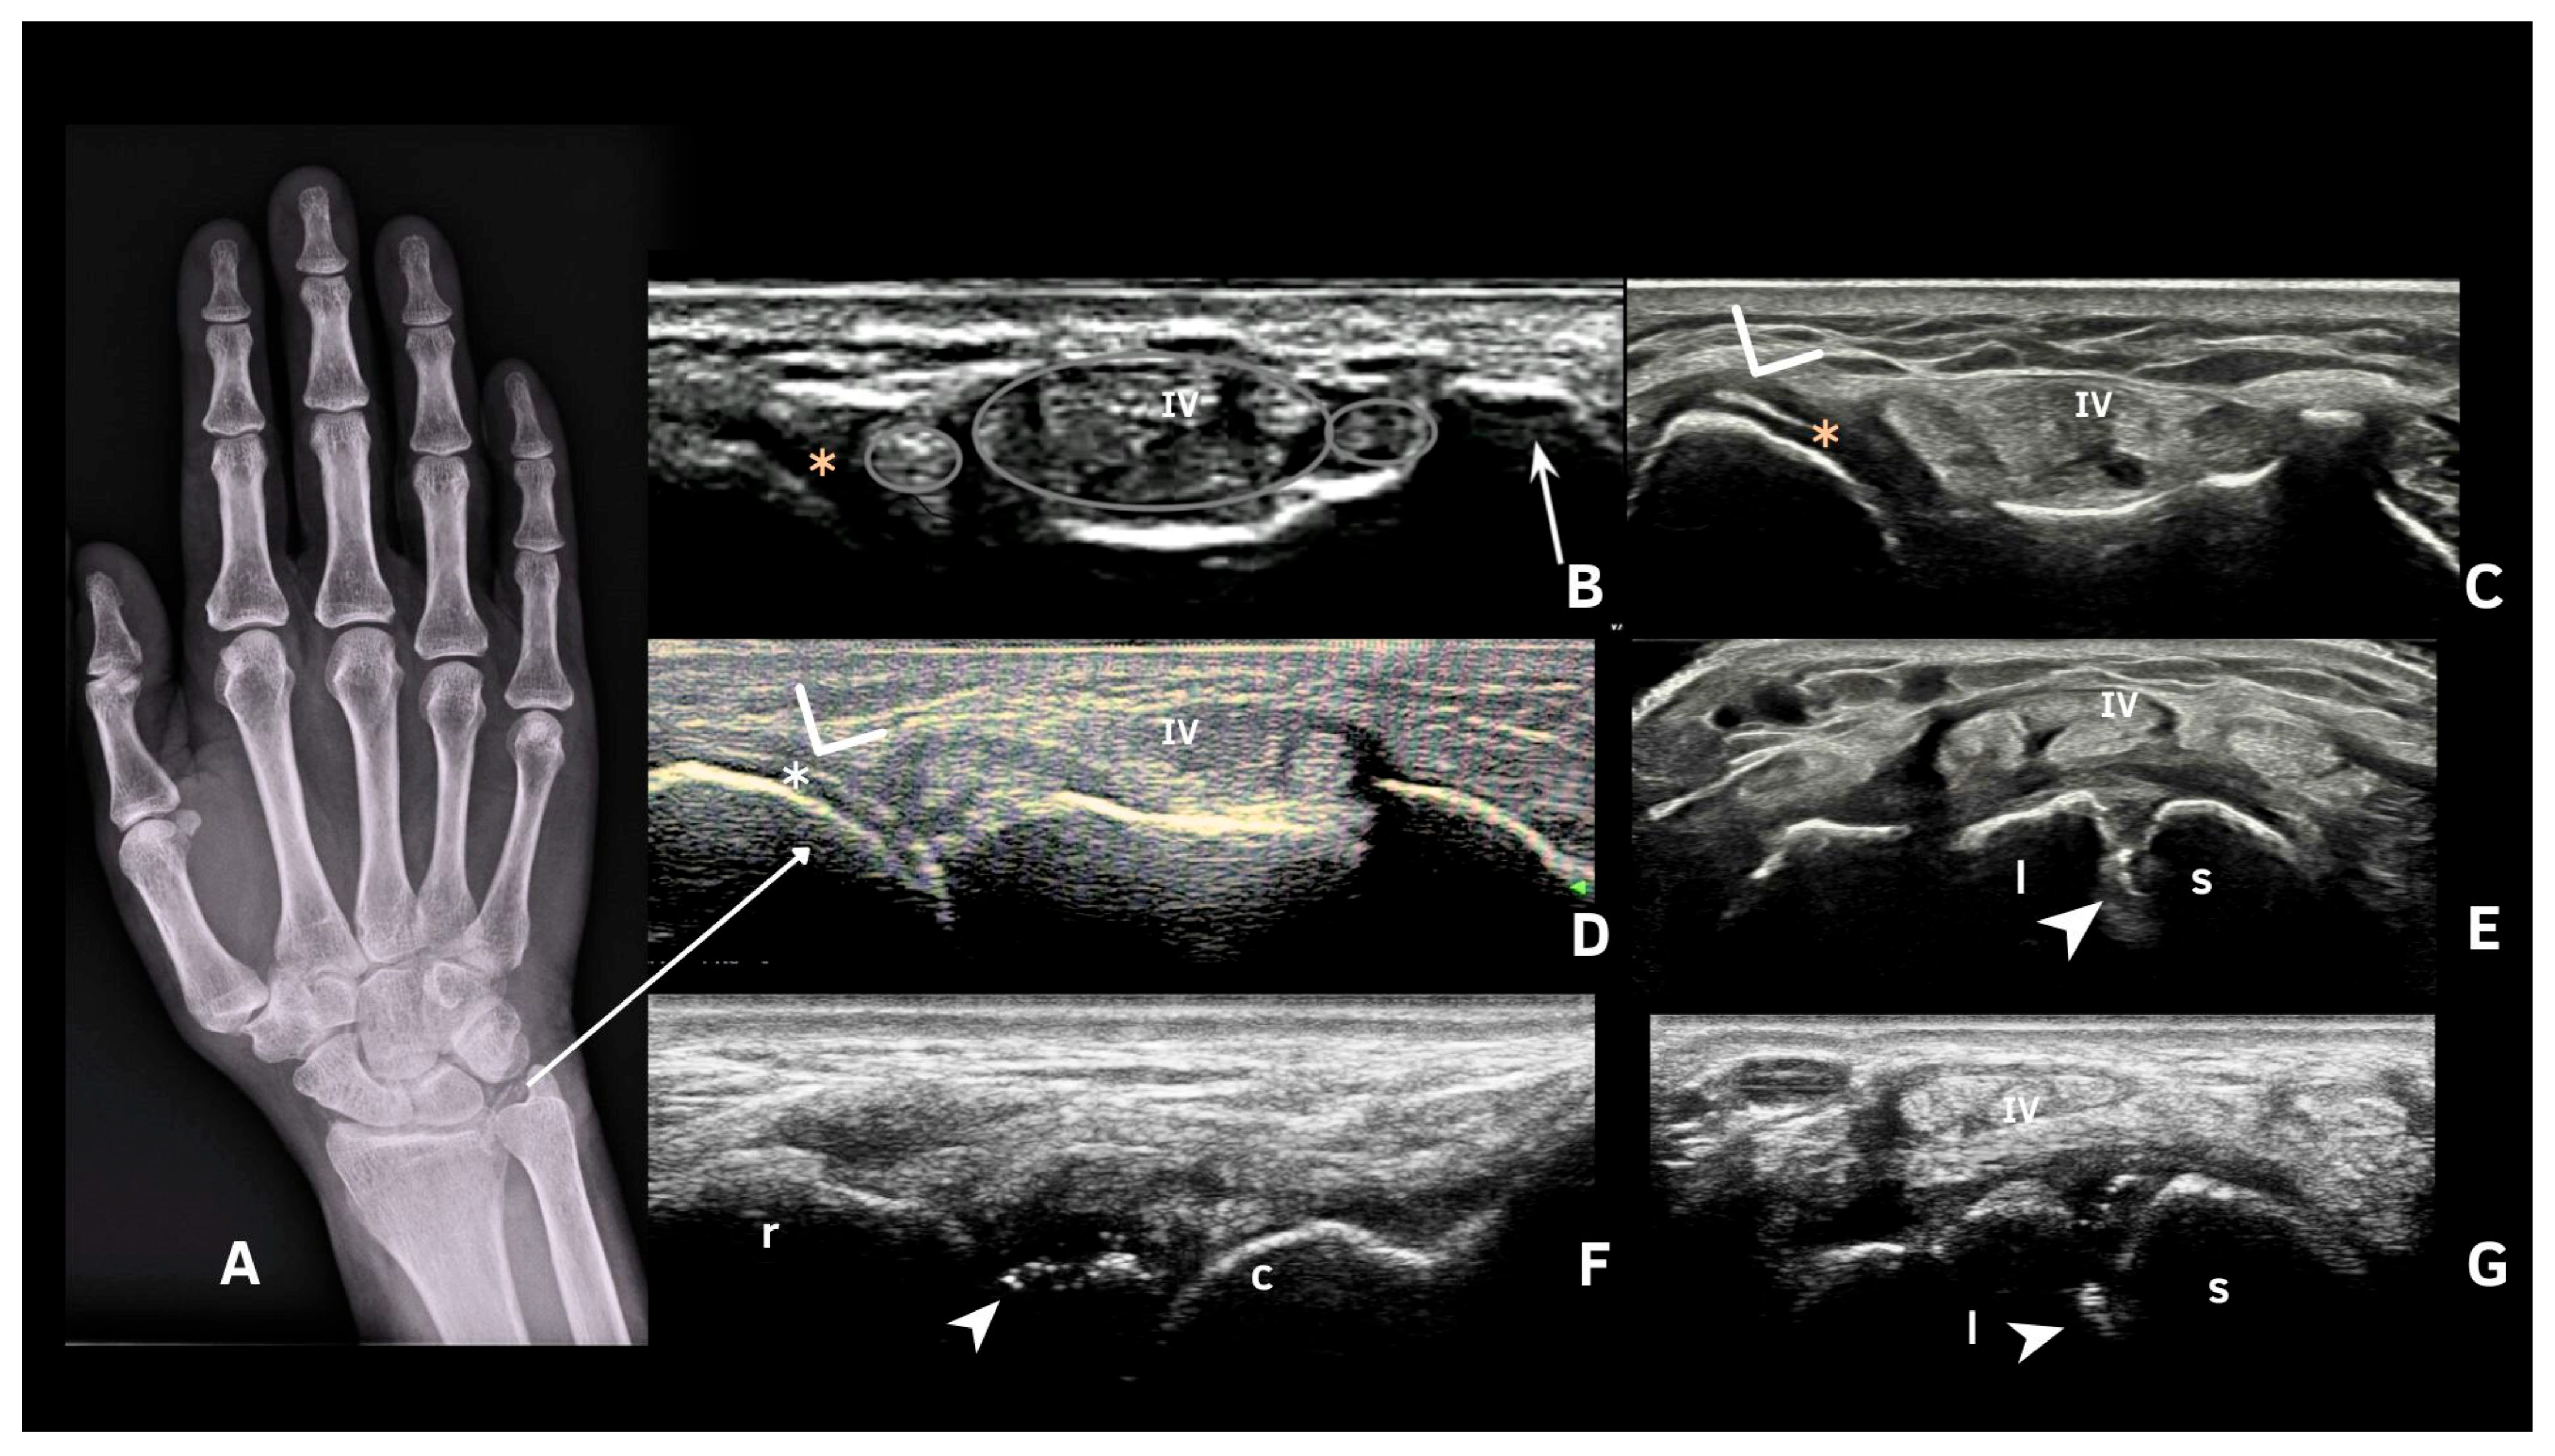

- Cipolletta, E.; Di Matteo, A.; Smerilli, G.; Di Carlo, M.; Di Battista, J.; Abhishek, A.; Grassi, W.; Filippucci, E. Ultrasound findings of calcium pyrophosphate deposition disease at metacarpophalangeal joints. Rheumatology 2022, 61, 3997–4005. [Google Scholar] [CrossRef]

- Cipolletta, E.; Smerilli, G.; Mashadi Mirza, R.; Di Matteo, A.; Carotti, M.; Salaffi, F.; Grassi, W.; Filippucci, E. Sonographic assessment of calcium pyrophosphate deposition disease at wrist. A focus on the dorsal scapho-lunate ligament. Jt. Bone Spine 2020, 87, 611–617. [Google Scholar] [CrossRef]